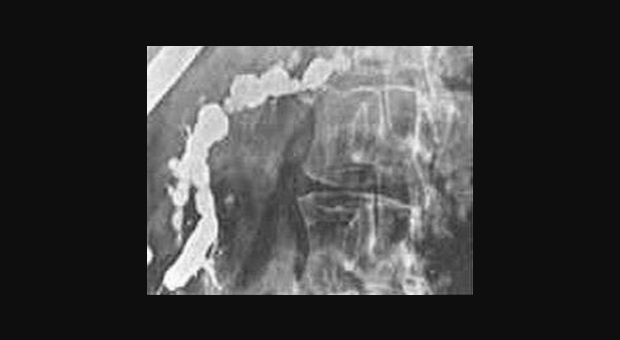

Иллюстрация №4: РХПГ при хроническом панкреатите (Изменения по типу "жемчужной нити")

Амилаза и липаза сыворотки может соответствовать норме или быть незначительно повышена. У 5-10 % пациентов с хроническим панкреатитом компрессия дистальной части общего желчного протока ведет к увеличению билирубина сыворотки и щелочной фосфотазы. Мальабсорбция жира ведет к увеличению его экскреции с калом (более 7 грамм в день). Выявление панкреатических кальцификатов при рентгенографии, УЗИ или компьютерной томографии является диагностическим критерием хронического панкреатита. Эти кальцификаты обнаруживаются в примерно 25-60 % всех случаев хронического алкогольного панкреатита и у 35-80 % пациентов с панкреатитом другой этиологии. Компьютерная томография может также выявить локальное увеличение размеров поджелудочной железы, ее атрофию, расширение панкреатического протока или псевдокисту. РХПГ является наиболее чувствительным и специфическим визуализирующим исследованием в диагностике хронического панкреатита (рис. 3).

Из-за риска развития панкреатита в результате выполнения РХПГ эта диагностическая процедура должна применяться только когда неинвазивные исследования являются малоинформативными. Новые, более современные виды исследований, как ядерно-резонансная холангиопанкреатография и эндоскопическое ультразвуковое исследование становятся все более популярными. Если с использованием всех этих визуализирующих исследований не удается подтвердить диагноз, то может быть выполнено тестирование функции поджелудочной железы со стимуляцией секретином или ХК [10]. Диагностический алгоритм приведен на рисунке 4.